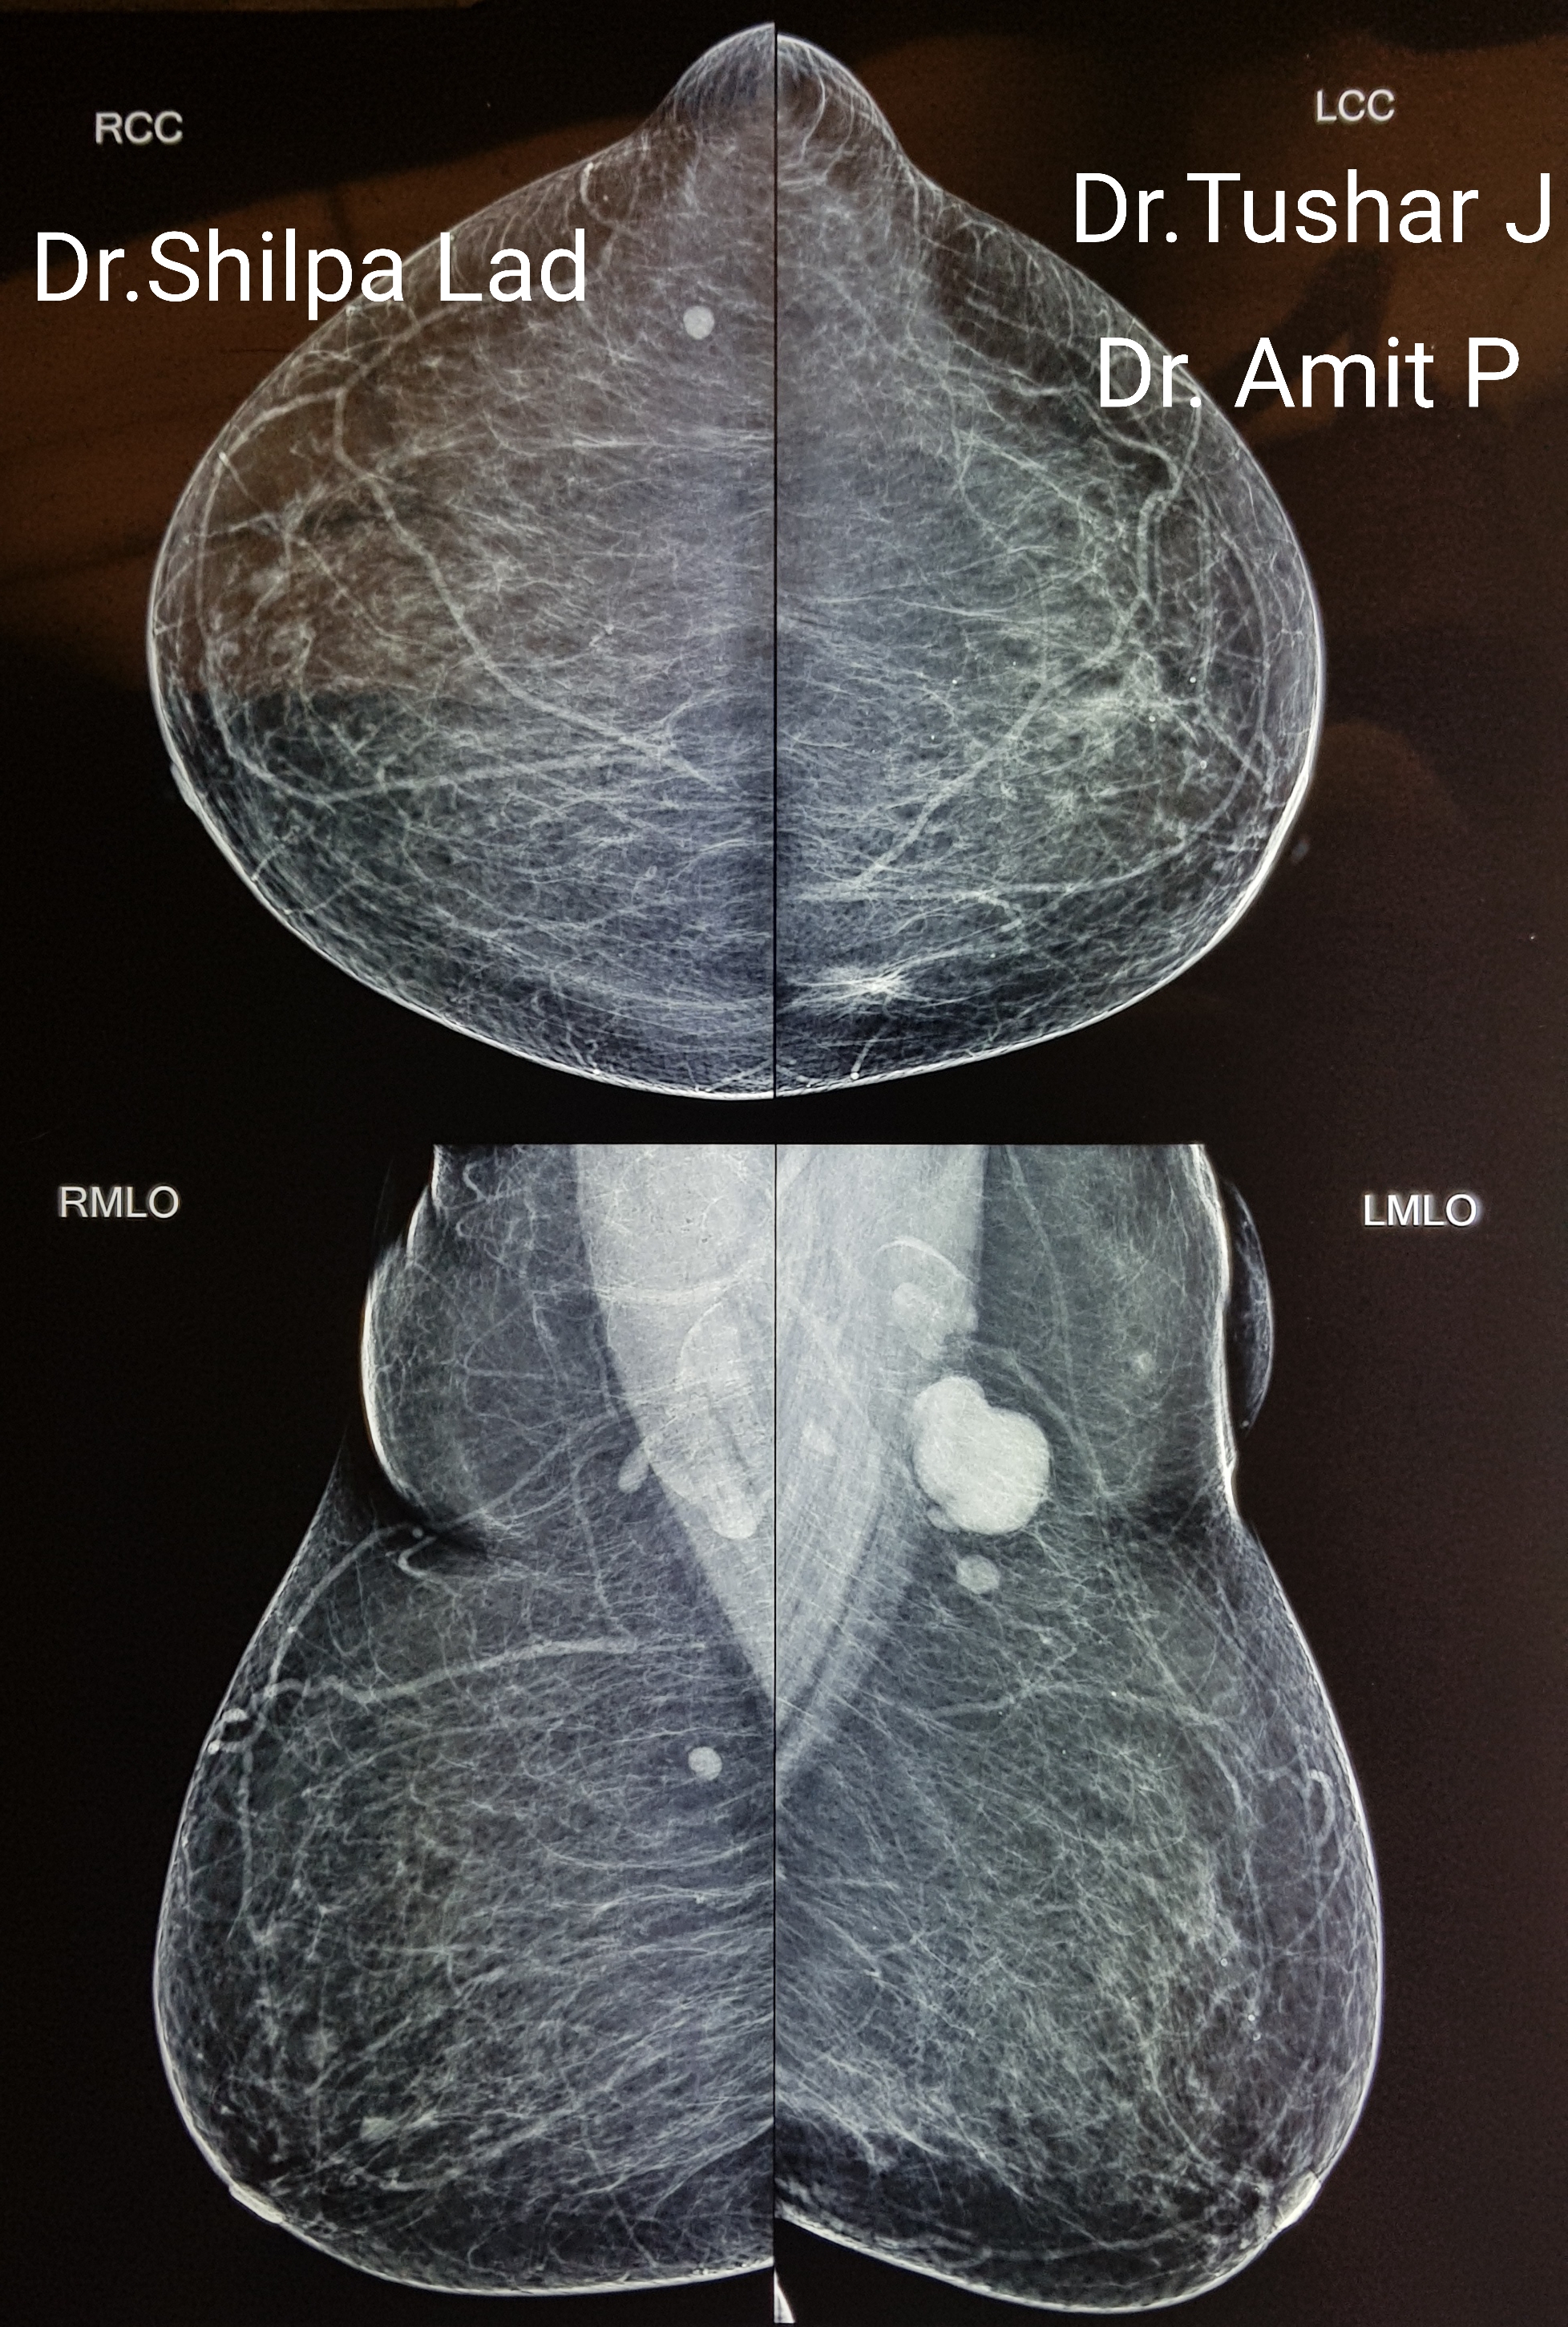

Reduction Oncomammoplasty